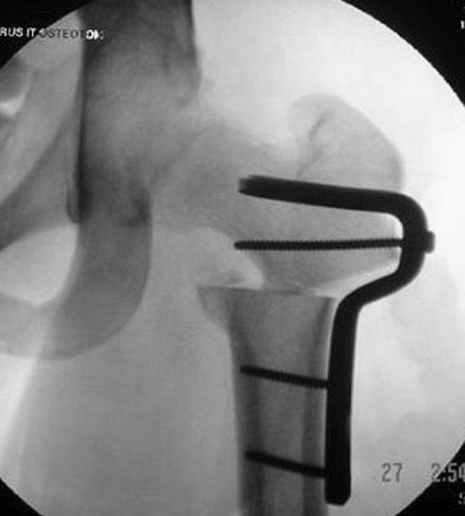

5:24 Рентгенограмма таза, вызывают врача ортопеда (снимок N1), его диагноз: закрытый переломо-вывих правого тазабедренного сустава, получает добро на закрытую репозицию в приемном отделении

5:38 Дважды неудачная попытка закрытой репозиции в приемном отделении

N 2

6:20 ответстенный врач принимает решение о репозиции в условиях операционной, предупреждаются родственники и больной, что при неудачной закрытой репозиции, о возможности открытой репозиции и фиксации задней стенки вертлужной впадины.

7:30 начало операции, больной на спине, попытка репозиции после анестезии N3, укладка больного на боку, доступ Kocher- Langenbeck, состояние седалищнего нерва около 2.5см кровоподтек, через joistick головка бедра приподнята, освобовождение сустава, фрагмент заднего края более 3х4 см репонирован на свое место. После промывания